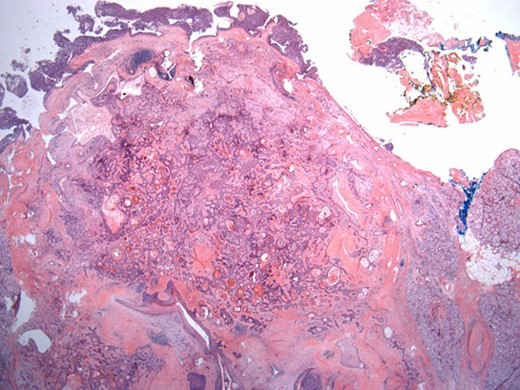

The surgical specimen showed a well-delineated submucosal nodule of 1.7 cm in the greatest diameter, without ulceration. Microscopically, this lesion appeared well defined with a central canal lined by keratinizing squamous epithelium without atypia (Fig. 2). In addition, we found confluent squamous foci with keratinizing centers (Fig. 3). The stroma was mostly fibrous, with occasional adipose and myxoid tissue. Only in the periphery of the lesion did we see a thin layer of normal ductal structures, highlighted by epithelial membrane antigen (EMA) positivity of the luminal cells, with immunochemistry studies (Fig. 4), whereas the other cellular component consisted of myoepithelial cells, highlighted by smooth muscle actin (SMA) and S100 protein (Fig. 5). No mucous secreting cell could be found. Keratin 5/6 and 903 were all positive for the whole specimen. The above-mentioned histopathologic findings helped to conclude the diagnosis of a PA with extensive squamous metaplasia. Margins were negative.

Solid sheets and massive squamous metaplasia with keratinization. Presence of adipose stroma. Hematoxylin and eosin (H&E ×40).